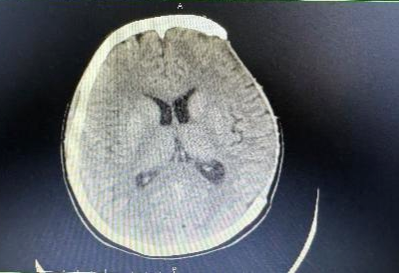

术后CT